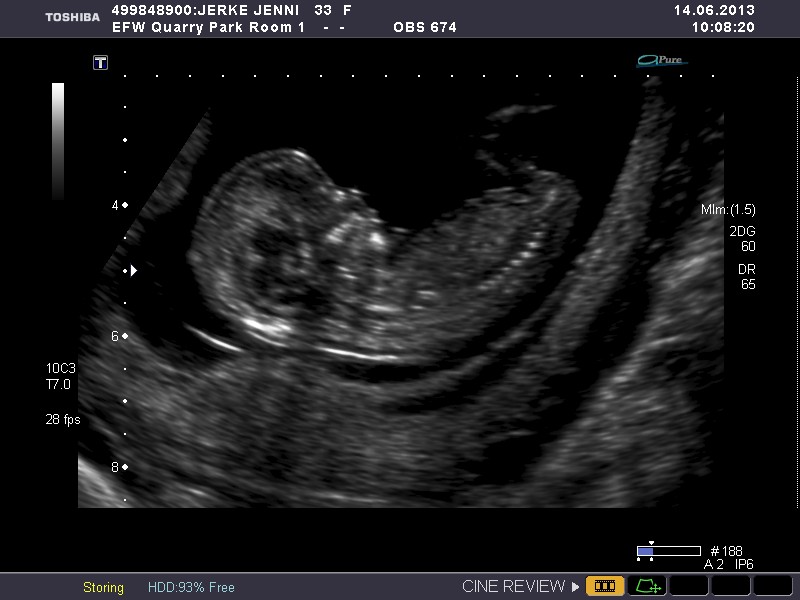

Please give me your best guess as to wether the baby in this ultrasound is a boy or girl.